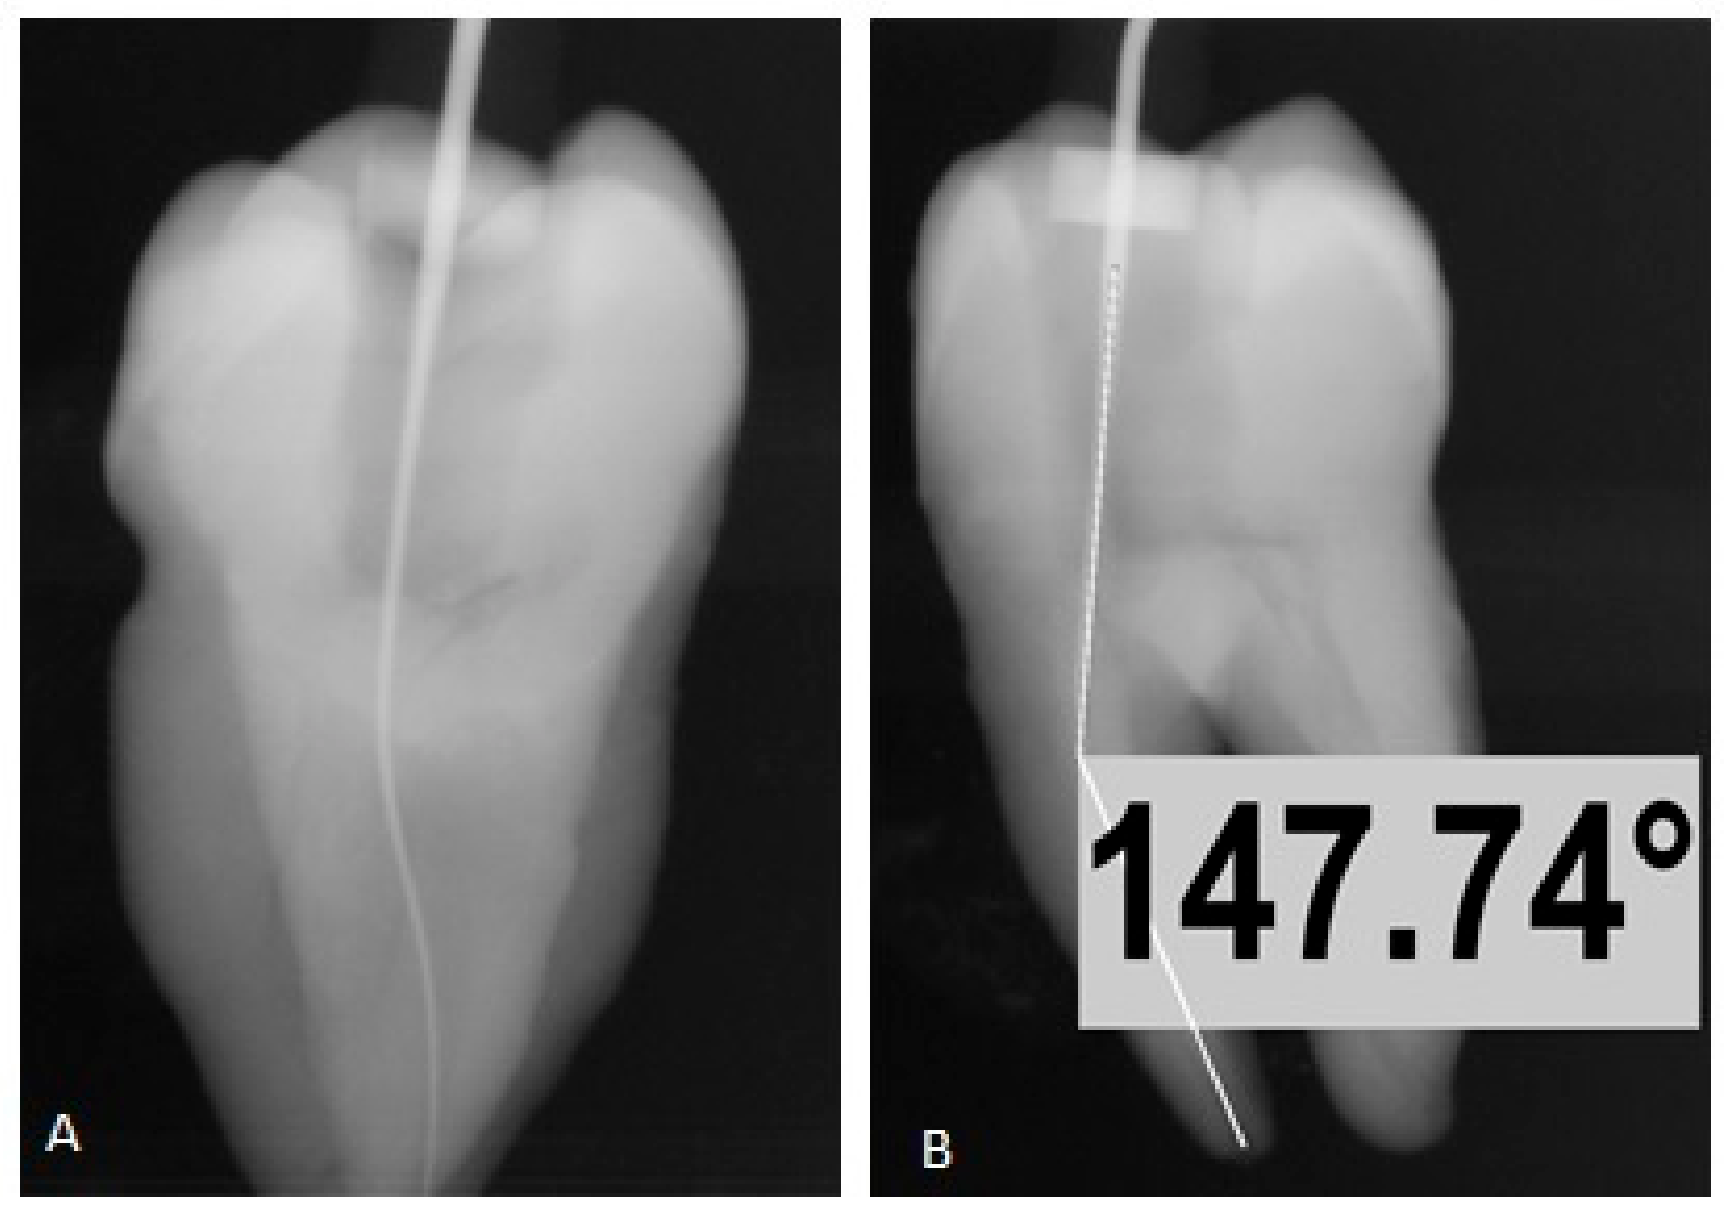

Digital images are obtained using the above-mentioned technique. These images were analyzed using the VixWin Pro digital image analyzing software (Gendex system) to obtain a straight line passing through the middle of the root. In case this is not obtained, the turn table was rotated, and another image was taken until a straight line was obtained (mimicking the straight instrument in the canal). Once a straight line was obtained, the turn table was rotated to 90 degrees and another image was taken. The instrument in the canal now was in its maximum curvature. The image indicates that the curved canal is made up of two segments, one was extending from the pulpal chamber floor down the long axis of the root as much as the coronal two thirds of the root and the second segment from the apex of the root extending back to the cervical to intercept the first line. These two lines intersect to form four angles. The interior angle is the estimate of the canal curvature. The angle of curvature, the radius, the height of curvature and the direction of curvature were calculated using VixWin Pro digital image analyzing software (using the angle measurement tool) (Figure 2).

Figure 2.

Image (A) shows straight instrument in the canal, Image (B) shows the maximum curvature of canal (180°–147.74° = 32.26°) after 90° rotation of turn table using plywood Jig.